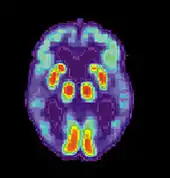

Maladie d'Alzheimer

La maladie d'Alzheimer (MA) est une maladie cérébrale progressive, dégénérative et fatale, dans laquelle est recensée une perte importante des cellules. Par conséquent, la mort des cellules cérébrales survient, bien que cette maladie soit la forme de démence la plus répandue[10]. À travers le monde, il existe 1 à 5 % de la population atteinte de la maladie d'Alzheimer[11]. Il est estimé que 500 000 Canadiens souffrent actuellement de la maladie d'Alzheimer ou d'une autre démence liée. Elle est la cause de handicap la plus répandue chez les individus âgés de 65 ans ou plus[10]. Les femmes sont disproportionnellement atteintes par cette maladie[12].